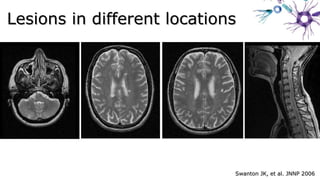

Swanton JK, et al. JNNP 2006Swanton JK, et al. JNNP 2006

Lesions in different locationsLesions in different locations

Swanton JK, etal. JNNP 2006Swanton JK, et al. JNNP 2006 Lesions in different locationsLesions in different locations